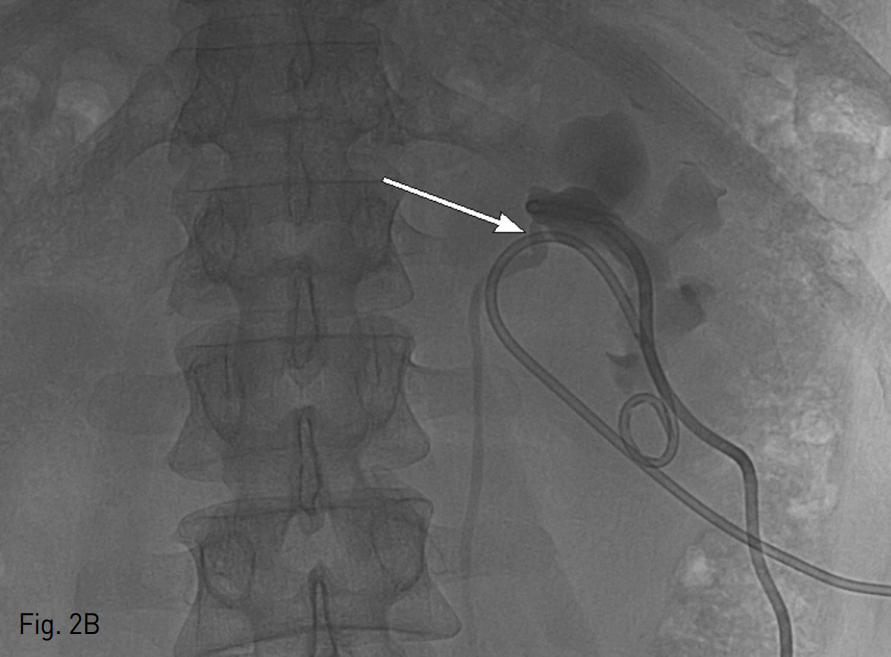

환자를 복와위로 눕힌 상태에서 초음파 유도 하에 21G Chiba needle을 이용하여 확장되어 있는 신배 (renal calyx)를 천자하고 0.018 inch hair wire를 삽입한 후 Yellow sheath (A&A M.D, Sungnam, Korea)를 이용하여 0.035 inch 유도철사 (0.035" hydrophilic guide wire, Terumo, Tokyo, Japan)로 guide wire를 교체하였다. 8.5 Fr pig tail catheter (Dawson-Mueller Drainage Catheter, Cook Medical, Bloomington, IN, USA)를 삽입하여 nephrostomy를 시행하였다. 선행성 요로조영술 (antegrade pyelography)를 시행했을 때 요관신우연결부위에 심한 협착과 함께 환자가 통증을 호소하였다 (Fig. 2A). 이후 다시 초음파 유도 하에 좌측신장의 단순낭종 내에 위에서 언급한 방법과 동일한 방법으로 배액관을 삽입한 뒤 단순낭종 내 있던 액체 40cc를 흡인하였다. 다시 선행성 요로조영술을 시행하였을 때 이전에 보이던 협착은 소실되었고 요관을 따라서 조영제가 잘 내려가는 것을 확인하였다 (Fig. 2B), 이를 근거로 요관 신우연결부위의 협착이 단순낭종에 의한 것임을 확인할 수 있었고 20cc의 99% 알코올을 이용하여 경화요법을 시행하였다.

Fig. 2

A. Antegrade pyelography shows significant narrowing of left ureter at the junction between renal pelvis and ureter (arrow).

B. Antegrade pyelography after renal cystic fluid aspiration shows mitigation of left ureteropelvic obstruction.